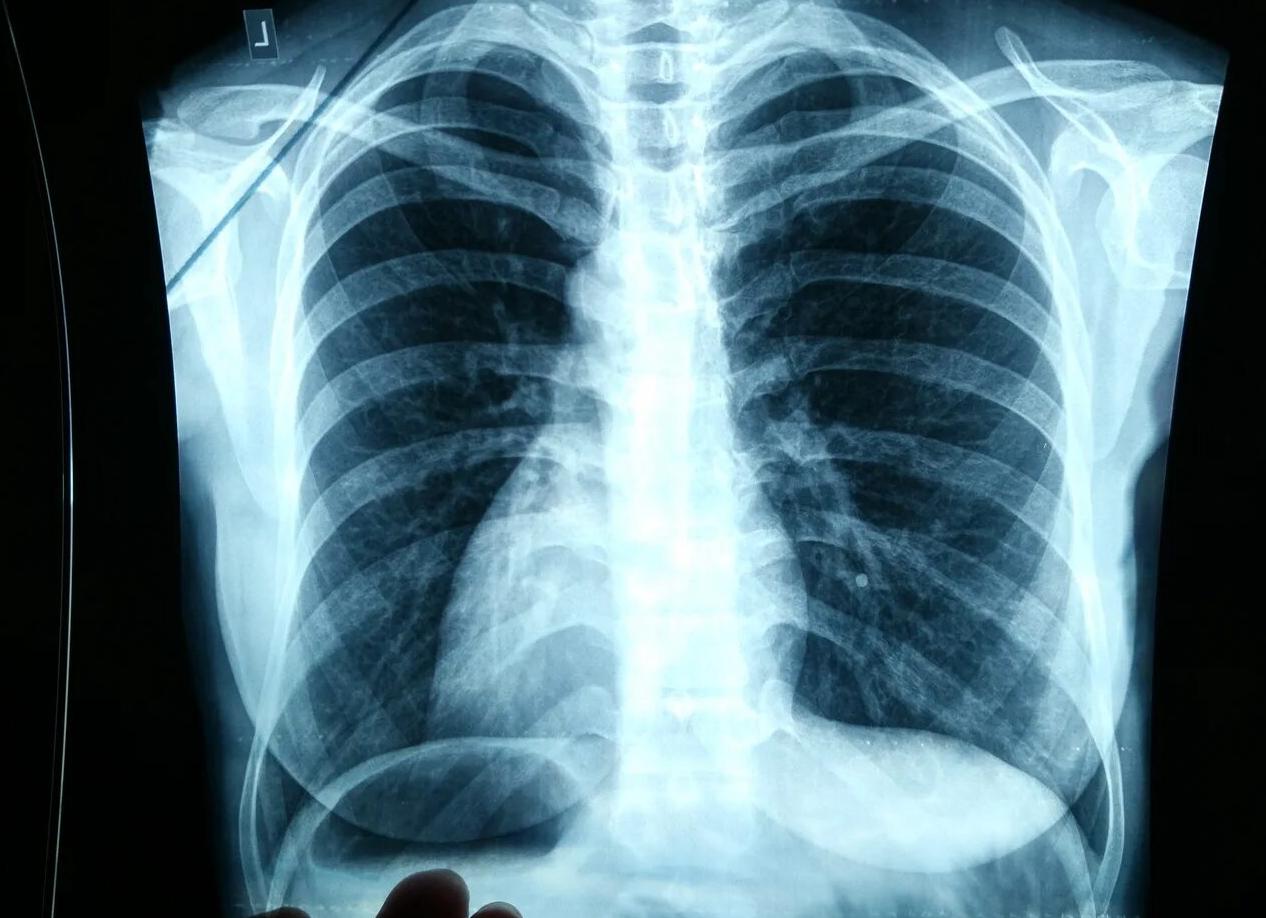

Да, конечно можно, даже нужно лицам старше 40-45 лет, особенно мужчинам. Флюорографию после 40 лет необходимо выполнять в двух проекциях, дабы исключить наличие новообразований. Сейчас даже делают снимок не из-за туберкулеза, а по причине высокого уровня раковых заболеваний.